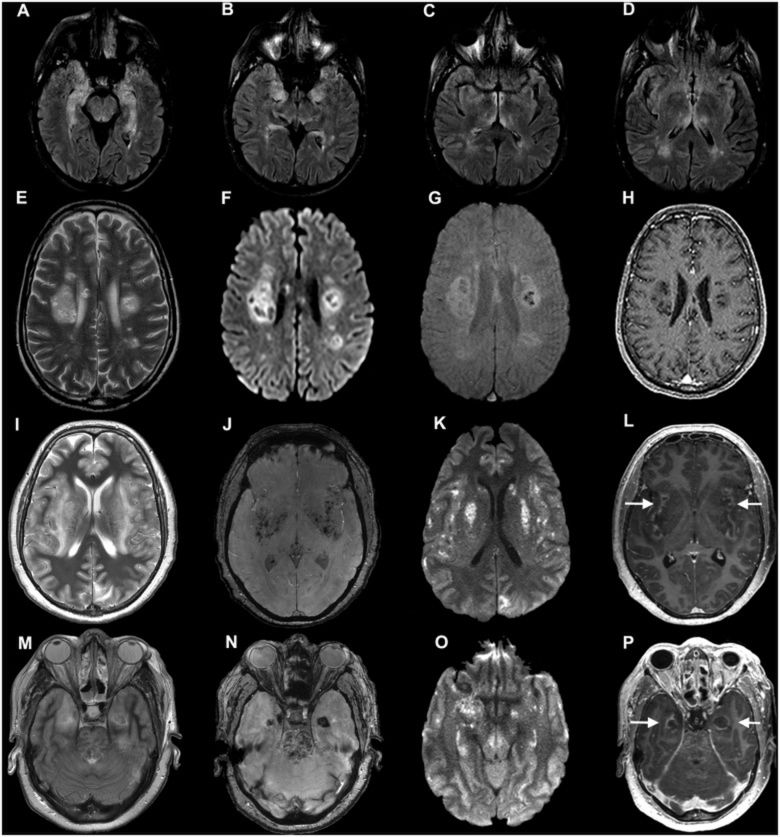

- Osoby, u których rezonans magnetyczny głowy oraz ocena płynu mózgowo-rdzeniowego nie wykryły zmian, z reguły przechodziły COVID-19 łagodniej. Ale osoby, u których doszło do rozwinięcia encefalopatii w przebiegu COVID-19, miały nawet 7-krotnie wyższe ryzyko zgonu - komentuje wyniki badań dr Adam Hirschfeld, neurolog z Oddziału Neurologii i Udarowego Centrum Medycznego HCP w Poznaniu.

Ból głowy może zwiastować ciężki przebieg COVID © Oxford University

- Bardzo ważne jest, aby nie przeoczyć zmian organicznych w strukturach mózgu. Dlatego osoby, które przeszły COVID-19 i doświadczyły ciężkich objawów neurologicznych, powinny przejść badania obrazujące. W niektórych przypadkach zakażenie SARS-CoV-2 może uaktywnić stare bądź utajone choroby. Musimy więc być bardzo czujni - podkreśla prof. Konrad Rejdak.